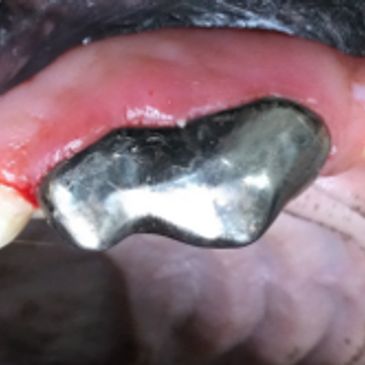

Extractions can often be complicated by severe periodontal disease, cyst formation, or unerupted teeth. Surgical ex tractions can be performed for complicated cases. Goals are to minimize bone loss. Bone graft placement can enhance new bone formation with the goal of maintaining bone height around the adjacent teeth.